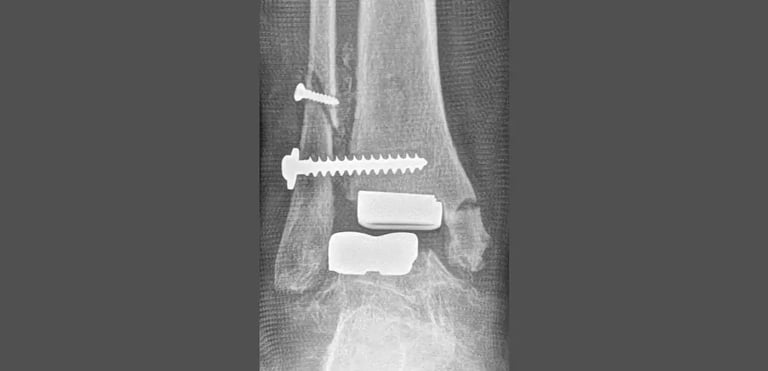

Grazie alla scelta di resurfacing programmata dal collega al momento del primo impianto, è stato possibile programmare la revisione mediante il posizionamento di una seconda protesi di caviglia “primo impianto”.

Il vantaggio di una protesi “primo impianto” rispetto ad una protesi da revisione è quello di “occupare meno spazio”, richiedere meno sacrificio osseo e lasciare aperta un’ulteriore strada alla revisione in caso di necessità.

Il risultato finale di una revisione, come nelle immagini che mostro, è una nuova protesi impiantata, con allineamento corretto e risparmio del bone-stock residuo.

L’obiettivo di una revisione, quando possibile, è quello di ottenere un impianto stabile, in asse, che abbia una vita lunga, il più lunga possibile ma per cui sia ancora possibile programmare una revisione in caso di necessità.